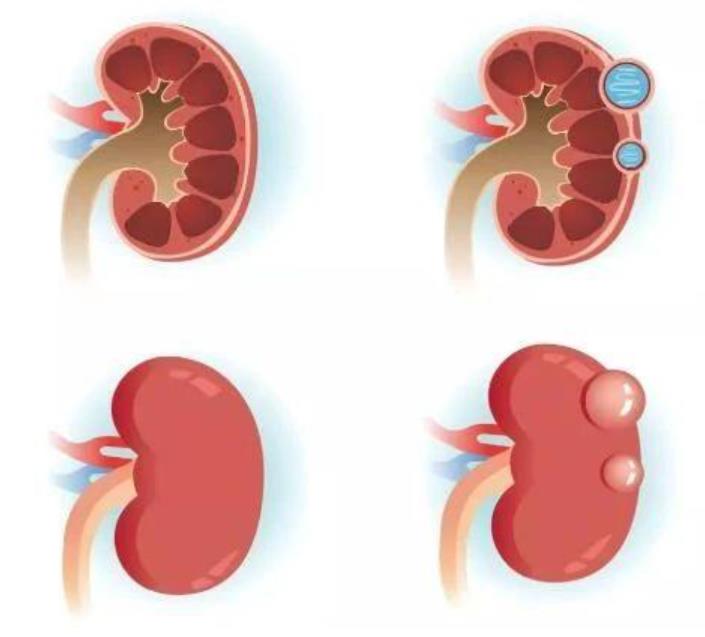

左侧2图正常肾脏,右侧2图为肾囊肿

肾脏是人体最容易发生囊肿的器官之一,通俗讲,就是肾脏内部或是外部形成了与外界不同的闭合性腔隙,囊壁细胞可分泌囊液,继而囊肿会逐渐增大。肾脏有很多疾病会产生肾脏囊性变,被称为“肾囊性疾病”,大体分为两类,一类是遗传性的,另外一类是非遗传性的。

非遗传性肾囊性疾病中,最常见的是单纯性囊肿 (临床中常说的散发性肾囊肿)、多发肾囊肿、获得性肾囊肿、肾盂旁囊肿等。